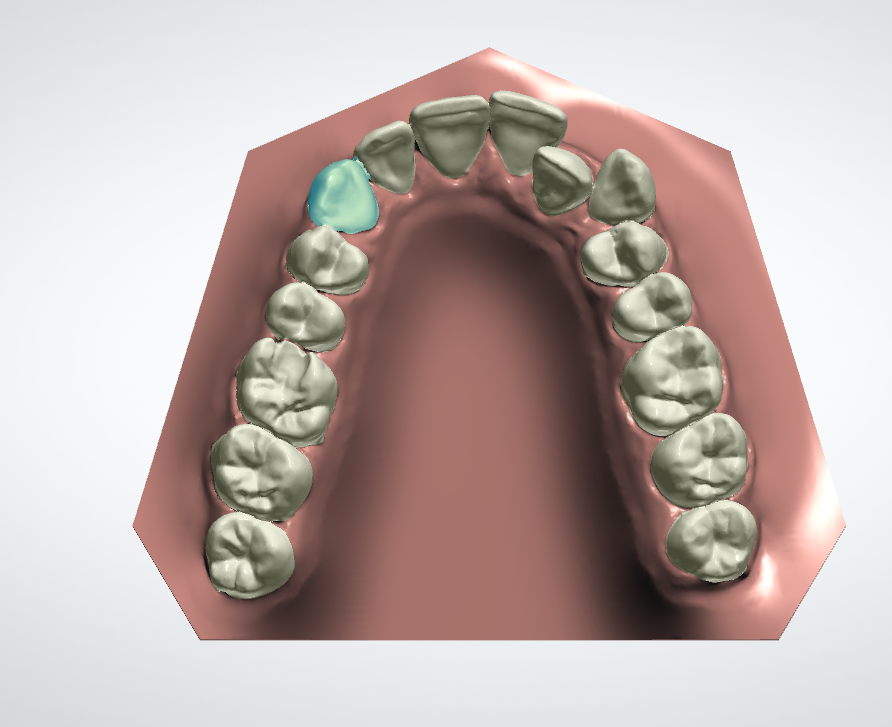

Полный расчет исходной ситуации в 3D цефалометрии. Составление плана лечения (ортосетап) в программе 3D Shape Ortodont.Загрузка КТ пациента-учет «движения корней» при лечении. Единственно правильный перенос положения брекетов или элайнеров - 3D печать полученного в программе результата (примеры представлены ниже на фото).